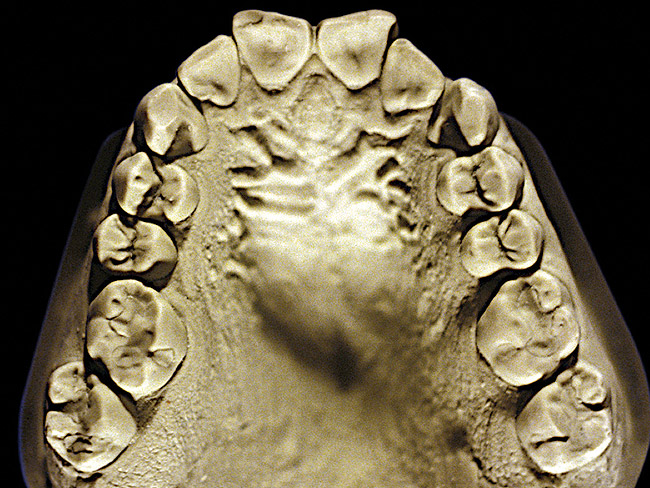

Figure 7  Moderate NCLTS from toothpaste, maxillary arch.

Figure 7

Figure 7 and Figure 8 are examples of NCLTS resulting from toothpaste. Upon examination, one could see that the overall anatomical detail of the teeth was faded with a sandblasted appearance. A closer view of the facial surfaces (Figure 9 and Figure 10) illustrates this to a greater degree and one can observe that the normal intricate facial anatomy was completely missing. It is interesting to note there was no cervical recession of the gingiva, even though every surface of every tooth had been abraded. This is due to the fact that this patient had always used a soft, round-ended filament toothbrush.21-22 This patient's sole desire regarding her oral hygiene was to get her teeth whiter.